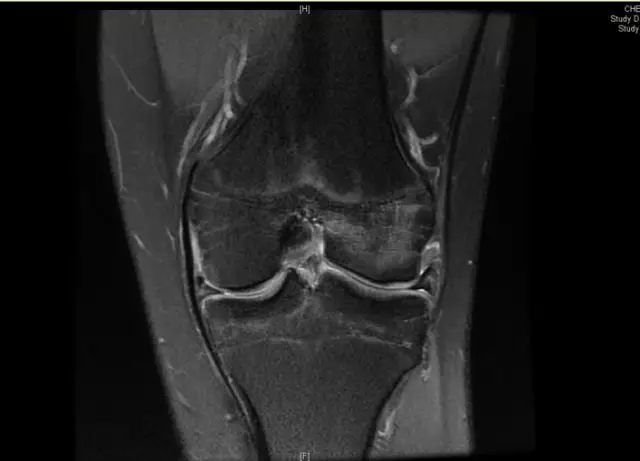

前交叉韧带断裂

从这个病例我们可以看到明显的股骨外髁骨擦伤,韧带的形态是中断的,大片的渗出病变,并且以胫骨平台的夹角变小,下止点可见部分信号增高,上止点可见大片的渗出病变,缺乏韧带止点应有的形态和张力,轴位片也可以看到内外上止点信号改变。所以这个病例考虑前交叉韧带断裂。